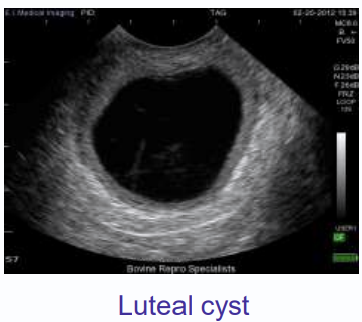

luteal cysts

thick walled, more than 3 mm thick

single cysts

produces mainly progesterone

clinical presentation luteal cyst

anestrus

why does a cow with luteal cyst commonly present with anestrus

negative feedback from increased progesterone